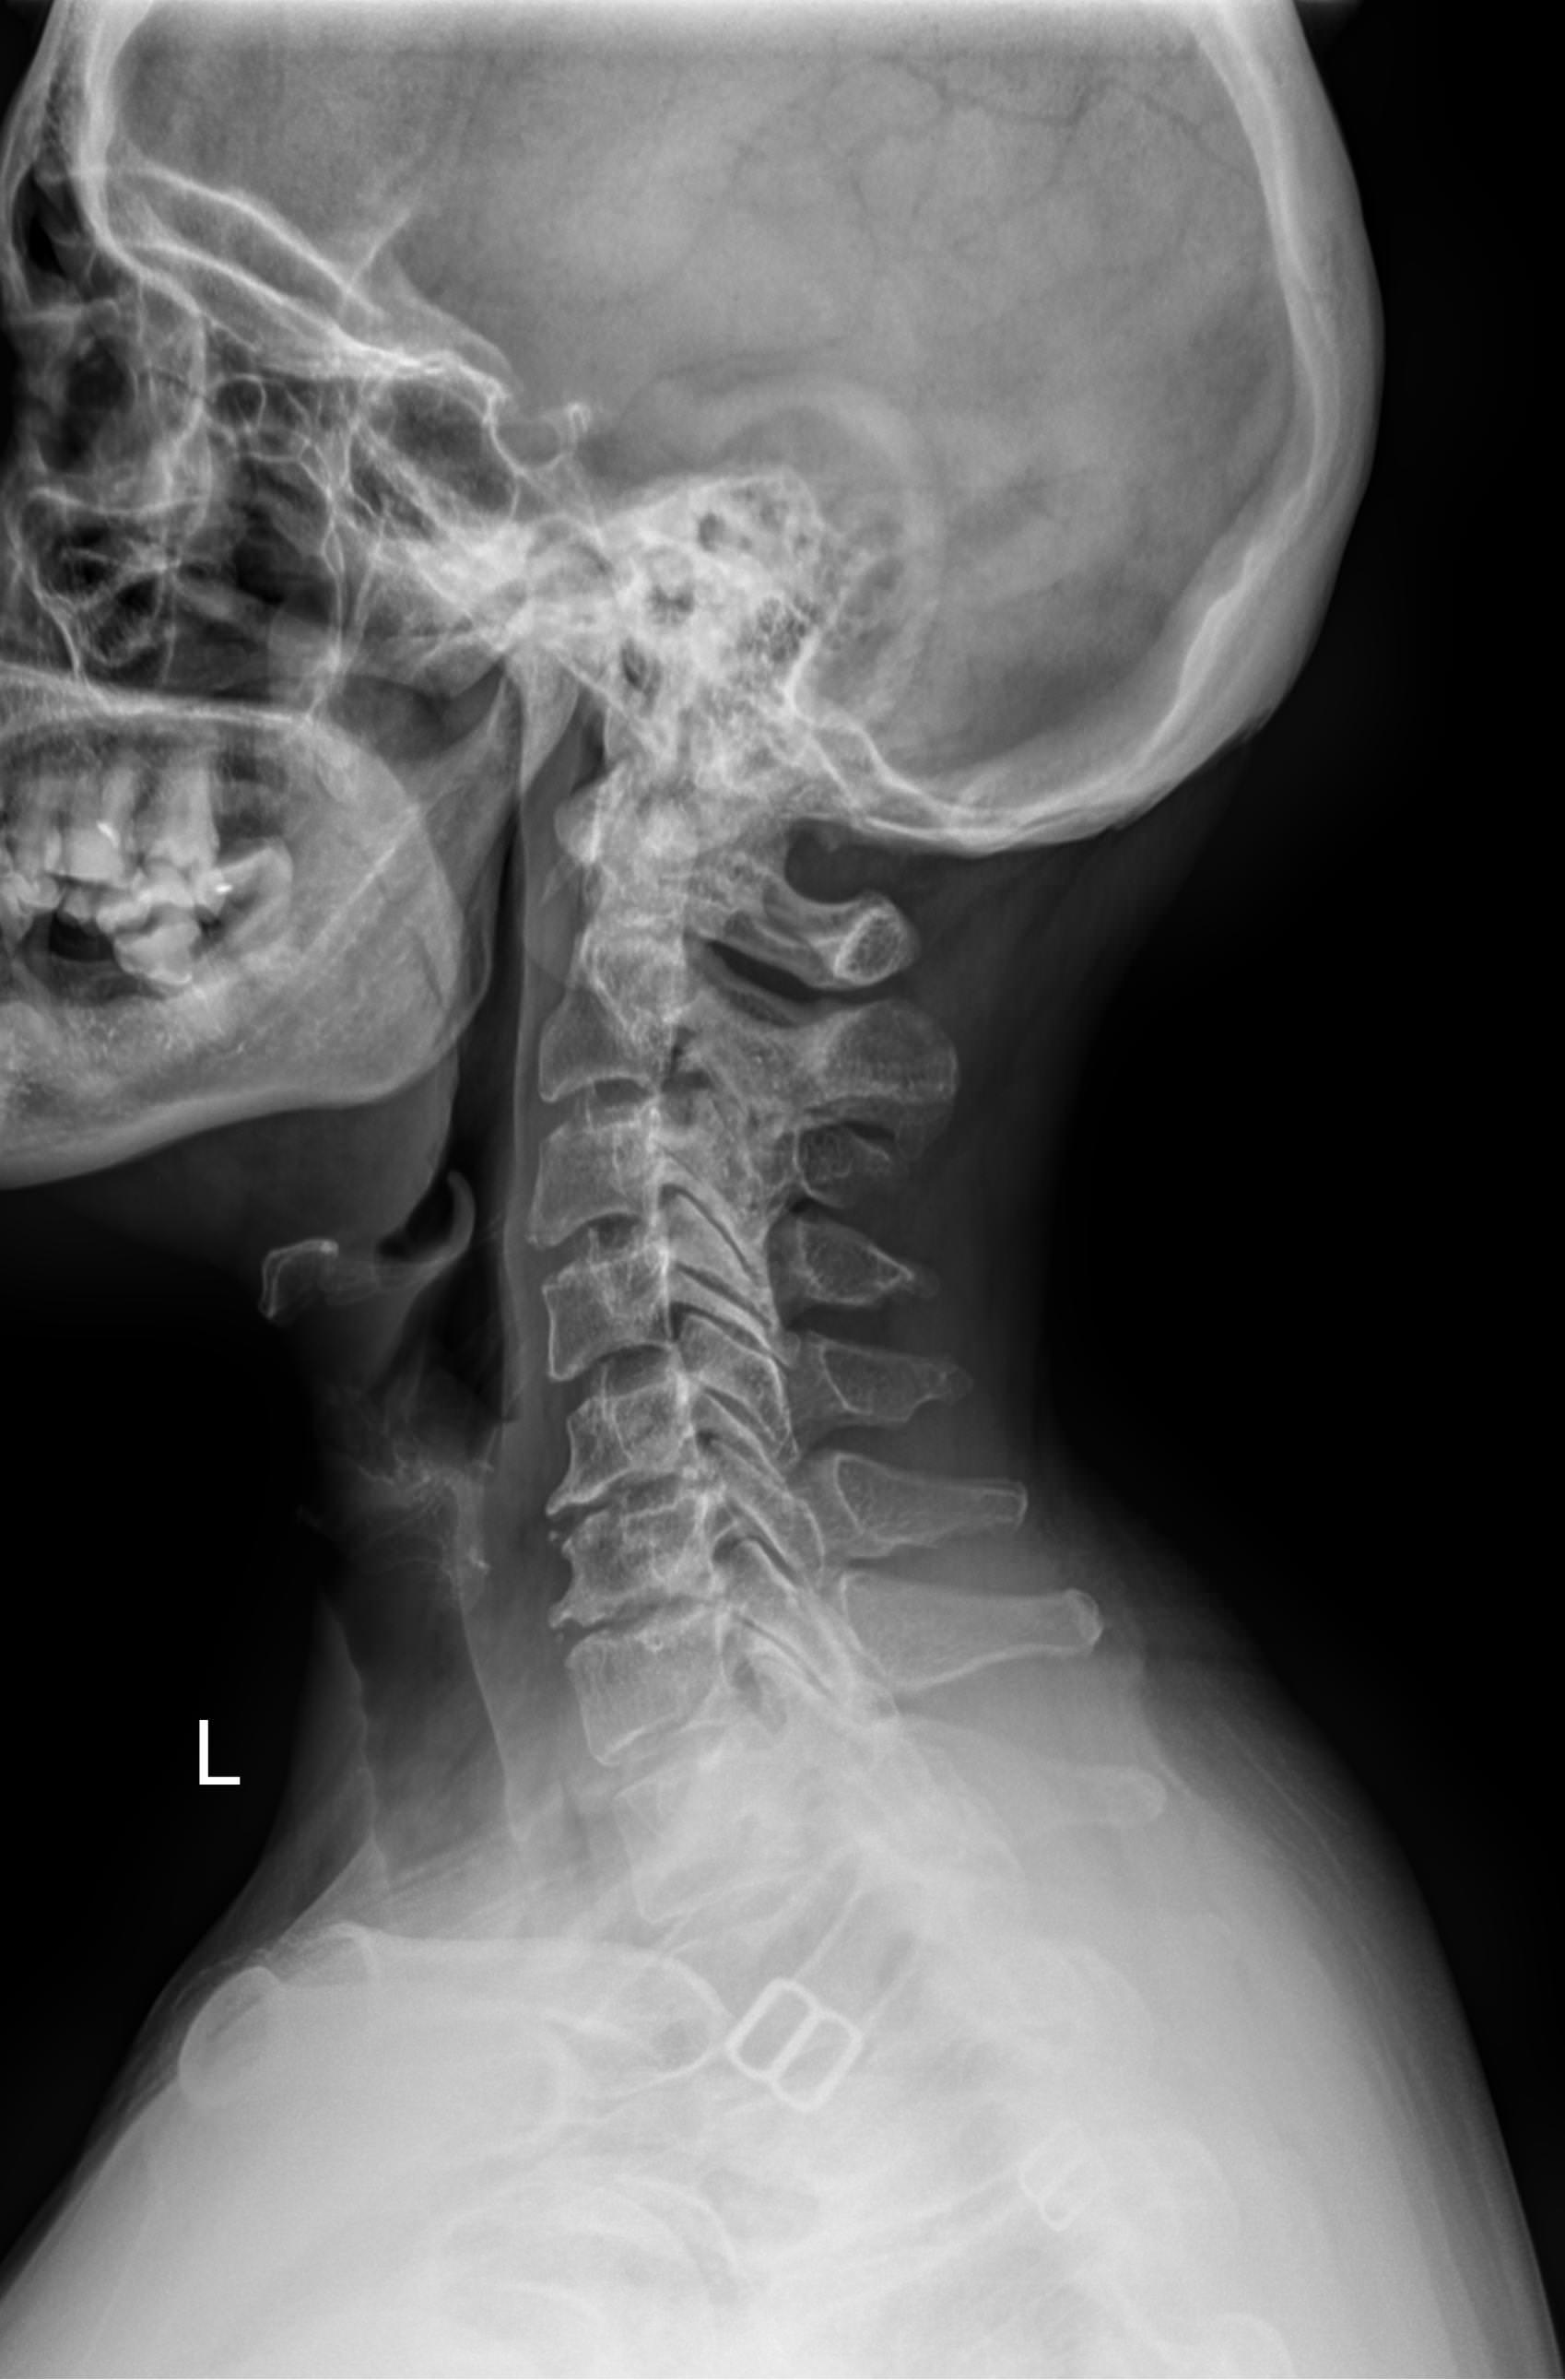

В качестве подготовки необходимо снять все металлические украшения с шеи и головы, расстегнуть пуговицы и надеть защитную накидку. Диагностика выполняется в положении стоя или сидя, всего делается 3 снимка:

• В боковой проекции ― строго боком к детекторной пластине;

• В условиях максимального разгибания головы назад;

• В положении максимального наклона головы вперед.